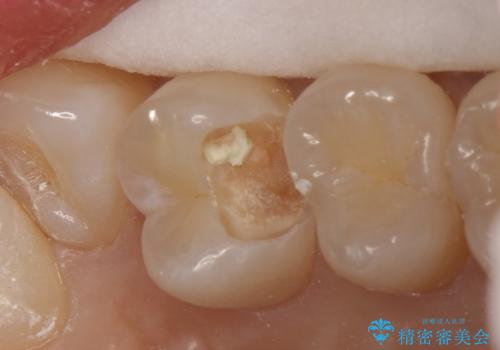

気づかないうちに大きな虫歯が 神経を保存し、セラミックで修復

- 神経を温存し、セラミックインレーによる修復をおこなった。

深い虫歯があった場合、たとえ神経を温存できたとしても長期的には痛みが出てきたり、神経がいつの間にか失活(正常な反応を失う)してしまったりするリスクはあります。

安易に神経を取り除くべきではありませんが、神経を保存するのであればそのようなリスクをよく理解していただく必要があります。